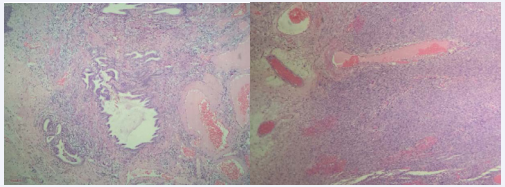

Both patients did not exhibit abdominal pain or distention and their computed tomography scansdid not reveal expansive pelvic process or metastatic disease (Figure 1).

Figure 1 Computed tomography scans evidencing the absence of distant disease and adnexal masses: A – absence of metastasis on the lungs; B – absence of metastasis  on the liver; C – absence of adnexal masses. (Images obtained from presented cases)

Figure 1 Computed tomography scans evidencing the absence of distant disease and adnexal masses: A – absence of metastasis on the lungs; B – absence of metastasis on the liver; C – absence of adnexal masses. (Images obtained from presented cases).